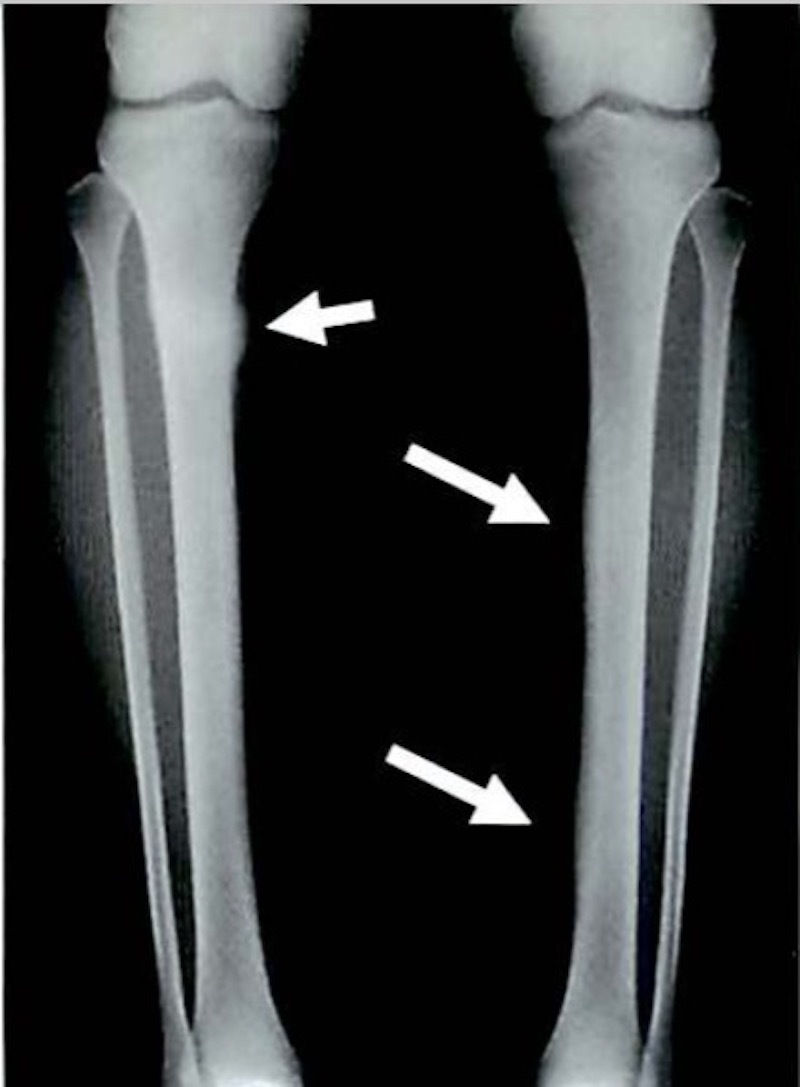

別名「過労性脛骨骨膜炎」とも呼ばれます。

下腿(膝より下の足)の下部1/3の部分に起こる痛みで

ランニングを過度に繰り返すことで出現する骨膜の炎症といわれています。

痛みは脛骨に沿っての運動時の全体的な鈍痛で始まり

悪化すると通常歩行時にも痛みが出現します。

ハードなトレーニングを集中的におこなったり、硬い地面の上でランニングを繰り返す、

過剰な筋トレ、過度の足趾背屈などが原因となることが多いです。